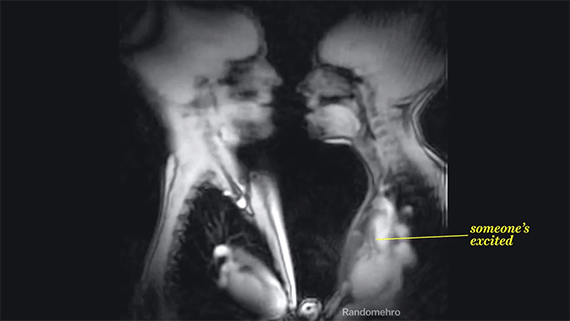

Ζευγάρι έκανε σεξ σε μαγνητικό τομογράφο -Κατέγραψαν τι συμβαίνει στο ανθρώπινο σώμα την ώρα της ερωτικής συνεύρεσης

Το γύρο του Διαδικτύου κάνει ένα βίντεο που έχει φτιαχτεί από διαδοχικές μαγνητικές που ελήφθησαν την ώρα που ένα ζευγάρι έκανε σεξ.

Μέσα από αυτές δίνεται η δυνατότητα κανείς να… ρίξει μια ματιά στο εσωτερικό του ανθρώπινο σώματος και να διαπιστώσει το τι συμβαίνει σε αυτό την ώρα που βρίσκεται σε σεξουαλική διέγερση. Tα όργανα που πάλλονται, τις καρδιές που χτυπούν δυνατά, τις εισπνοές και τις εκπνοές κατά τη διάρκεια των φιλιών. Αυτό που προκαλεί εντύπωση είναι το πώς όλο το ανθρώπινο σώμα συμμετέχει στη διαδικασία και πόσο σύνθετη αυτή είναι.

Παρακάτω παρατίθεται μια κινούμενη εικόνα που δείχνει το τι συμβαίνει στο ανθρώπινο σώμα όταν ένας άνδρας και μια γυναίκα ανταλλάσσουν ένα καυτό γαλλικό φιλί.

Η ερωτική συνέρευση έγινε για τις ανάγκες της… επιστήμης και ο μαγνητικός στον οποίο ξάπλωσε το ζευγάρι δεν τους «κεραυνοβόλησε» με βλαβερή ακτινοβολία.